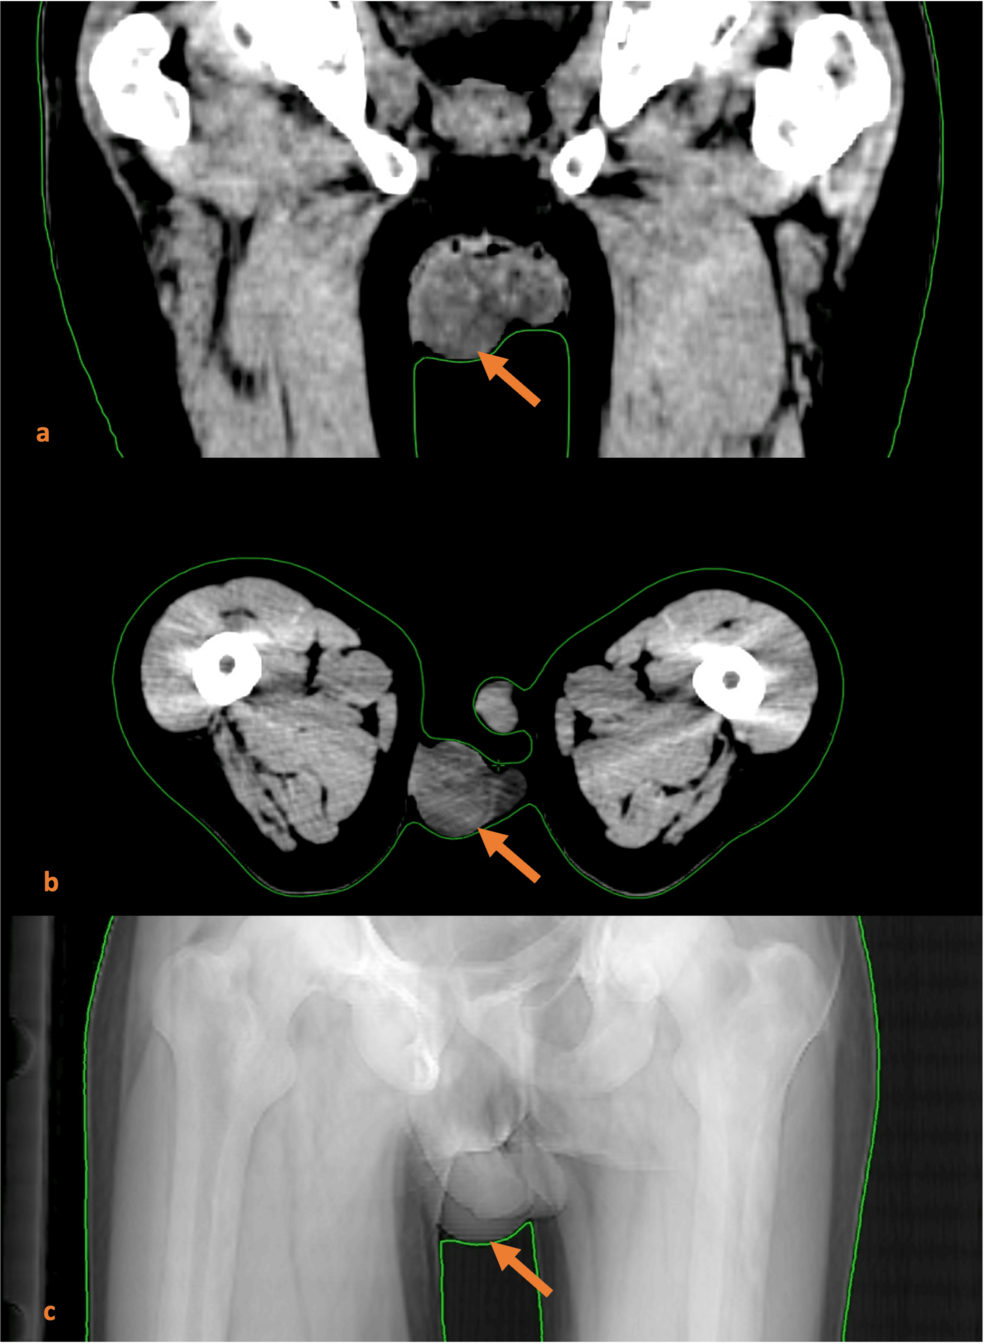

| Scrotal ultrasound | Heterogeneous hypoechoic lesion, 2.8 cm, with increased vascular flow on Doppler. | First‑line imaging to differentiate primary testicular tumor from metastasis. |

| Chest CT (contrast) | Central hilar mass (4.5 cm) in the right upper lobe with mediastinal lymphadenopathy. | Identifies primary lung lesion typical of small‑cell carcinoma. |

| Abdominal‑pelvic CT | No retroperitoneal nodes; mild hepatic steatosis. | Excludes common metastatic sites (liver, adrenal). |

| PET‑CT | SUVmax 12.5 in lung primary, 9.8 in left testis, mild uptake in mediastinal nodes. | Confirms metabolic activity of testicular lesion, supporting metastatic disease. |

- Day 0 – Patient presents with left testicular swelling; scrotal ultrasound performed.

- Day 5 – Chest CT identifies central lung mass; PET‑CT confirms metastatic pattern.

- Day 10 – Orchiectomy performed; pathology confirms SCLC metastasis.